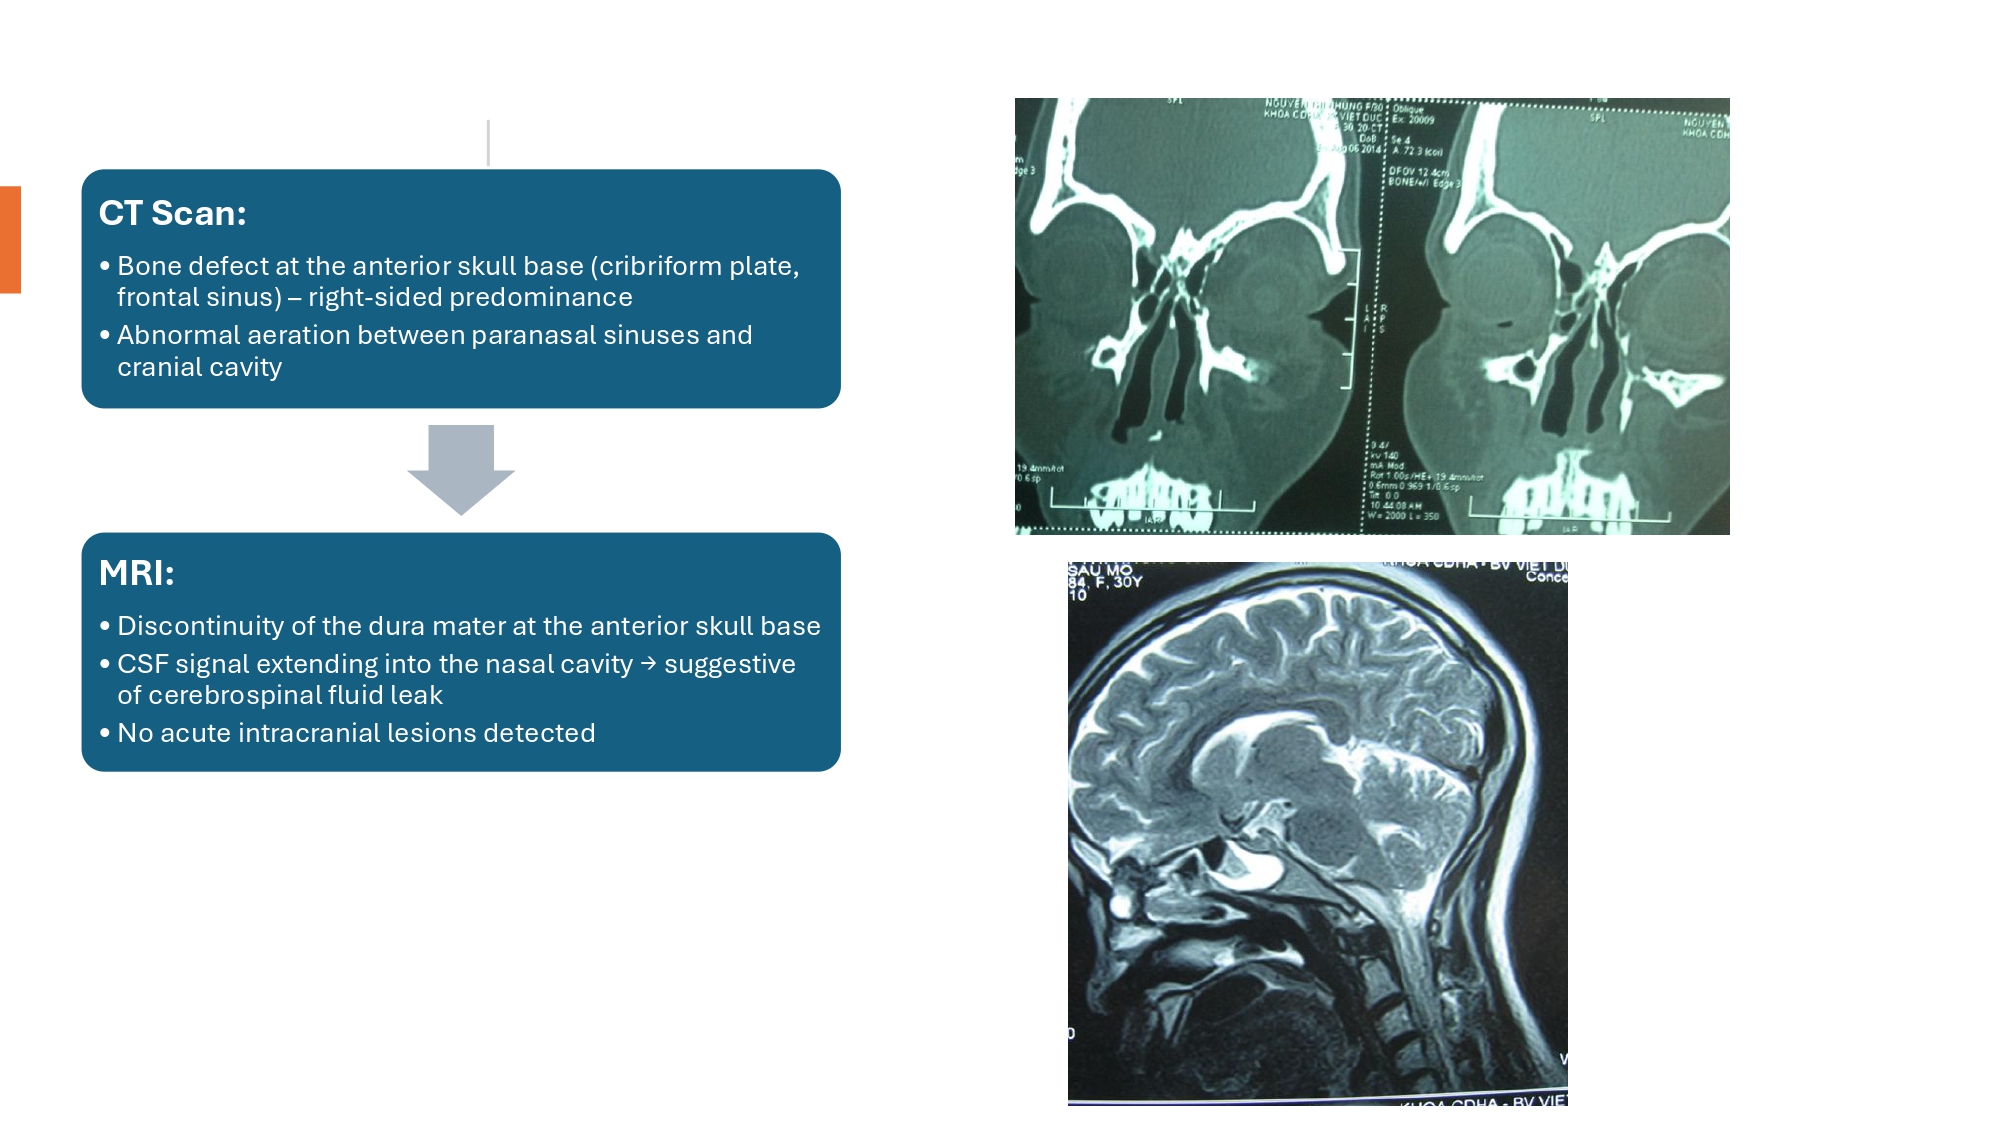

| 08:40 - 09:20 | Diagnosis of skull base trauma Post-traumatic CSF leakage | Assoc. Prof. Dong Van He Assoc. Prof. Kieu Dinh Hung | |

| 11:05 - 12:00 | Interactive Case Demonstration and Discussion I ~20 minutes each, (5 minutes presentation followed by 15 minutes discussion) Practicals: How I am doing it? Participants present case presentations about how they do it? The faculty comment on and discussion. 1. ICP management: How I am doing it? - Assoc. Prof. Duong Dai Ha 2. CSF leakage management: How I am doing it? - Assoc. Prof. Nguyen Thanh Bac | Prof. Christian Matula International & local faculties Participants | |